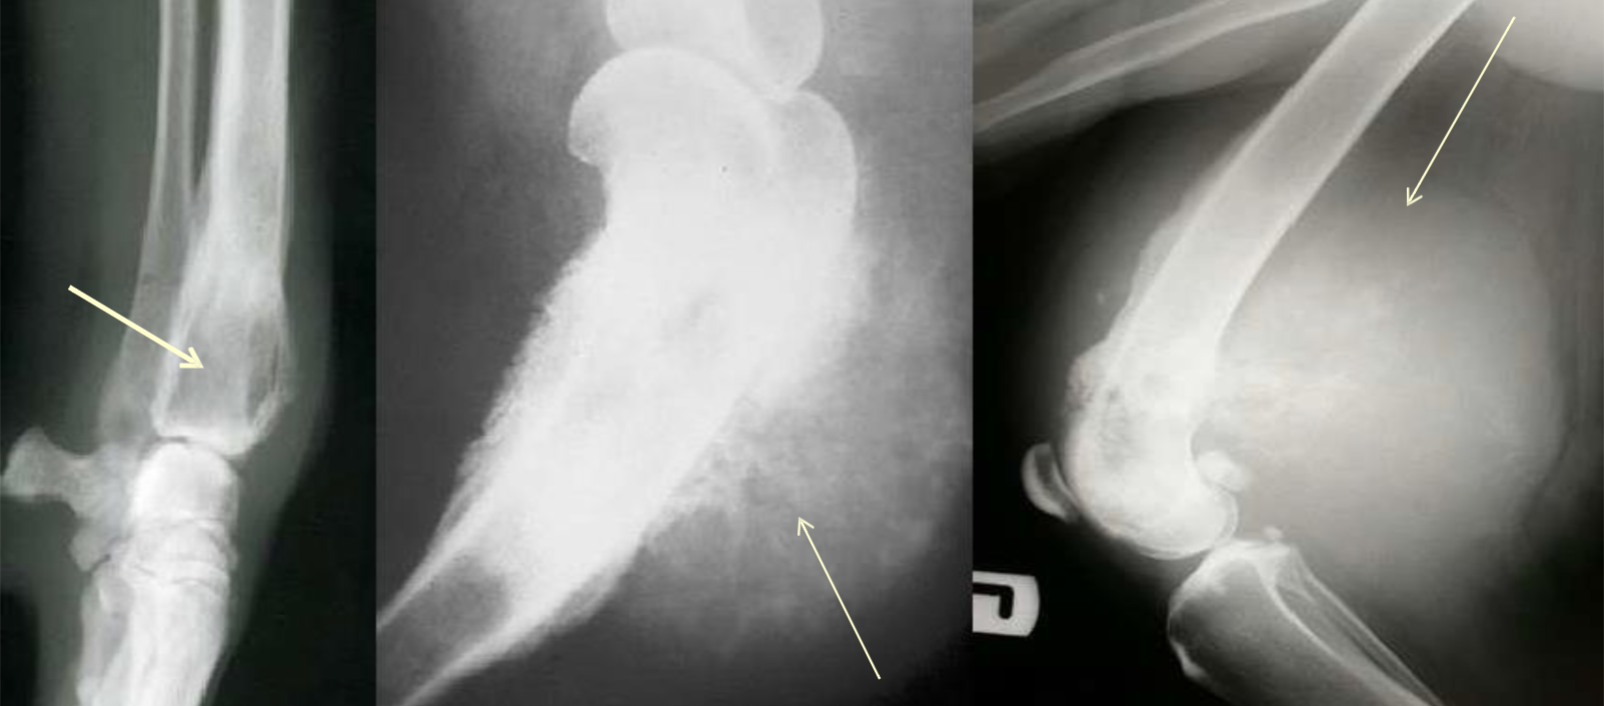

name the three form of oseosarcomas from left to right

lytic, sunburst, mass